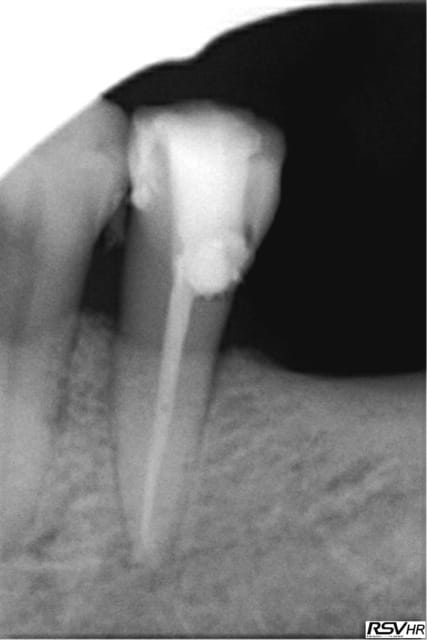

Ce sont des cones dentsply mais pas les réciprocs. je les scelle au tubuli seal en pompant un peu ( d'ailleurs sur la 25 ci dessous qui avait un 4eme ca a fait un dépassement preuve que ca fuse) je les coupe ensuite au système B avec le pluggeur qui sert à faire le bouchon apical.

Tres pratique d'ailleurs pour faire le cas échéant les tenons dans la séance de l'endo, l'empreinte et la provisoire dans la foulée.

Tu as fait des progrès. Disons par exemple que sur la deuxième prémolaire, tu es allé un poil trop loin, ce qui a réduit sérieusement la constriction apicale. Peut être que que tu mesures ta LT un demi millimètre plus longue que nécessaire.

La 25 bouchon apical système B + mac spaden pour la partie coronaire. Tu as vu je prend mes précautions pour débuter, ca ne me plait pas trop ces engins qui tournent à 40 000 tours dans un canal-))

Il faut que je trouve la bonne taille ici thermo compacteur noir (40 centièmes).